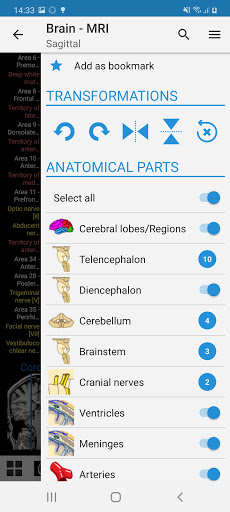

- Seleccione las etiquetas anatómicas por categoría

-El modo pines tiene un nuevo comportamiento que le permite seguir una estructura anatómica mucho más fácilmente

-Ahora puede seleccionar manualmente el tamaño de fuente que prefiere para sus etiquetas de estructuras anatómicas (en modo etiquetas)

-Dentro de la vista de detalles de una estructura anatómica , un alfiler ahora señala la estructura relacionada en todas las imágenes presentes

También toque directamente en la imagen para navegar a la imagen presentada en ese módulo

- Ahora puede ocultar las estructuras una por una (nuevo botón dentro de la ventana emergente de descripción) y visualizarlas nuevamente en el menú derecho